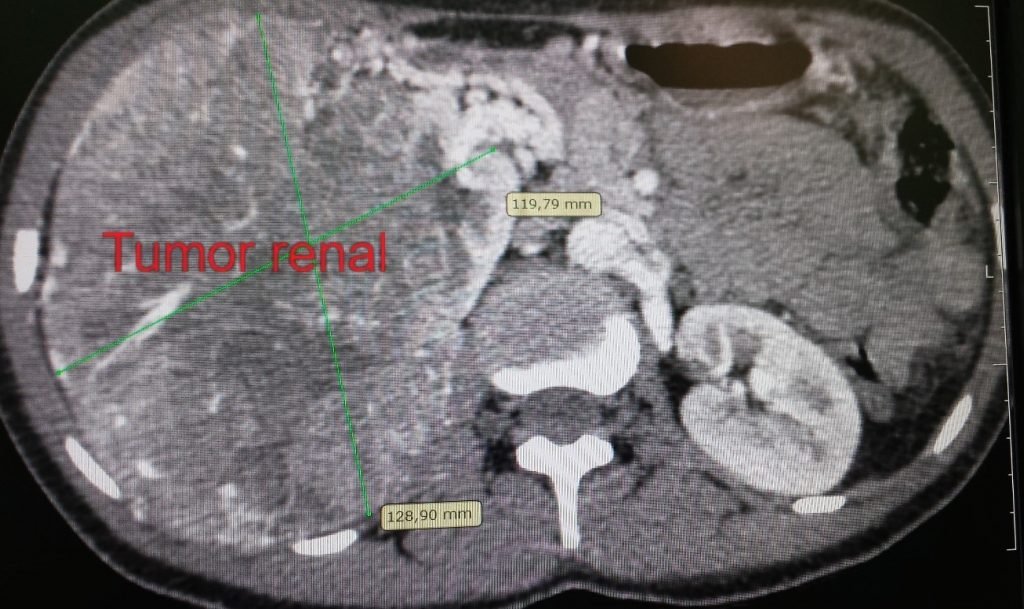

- A Tomografia Computadorizada (TC) de abdome e pelve com contraste é o padrão-ouro para diagnóstico e estadiamento.

- T1: Tumor ≤ 7 cm, restrito ao rim.

- T2: Tumor > 7 cm, restrito ao rim.

- T3: O tumor invade grandes veias ou o tecido perirrenal, mas não ultrapassa a fáscia de Gerota.

- T4: O tumor invade além da fáscia de Gerota ou a glândula adrenal ipsilateral.